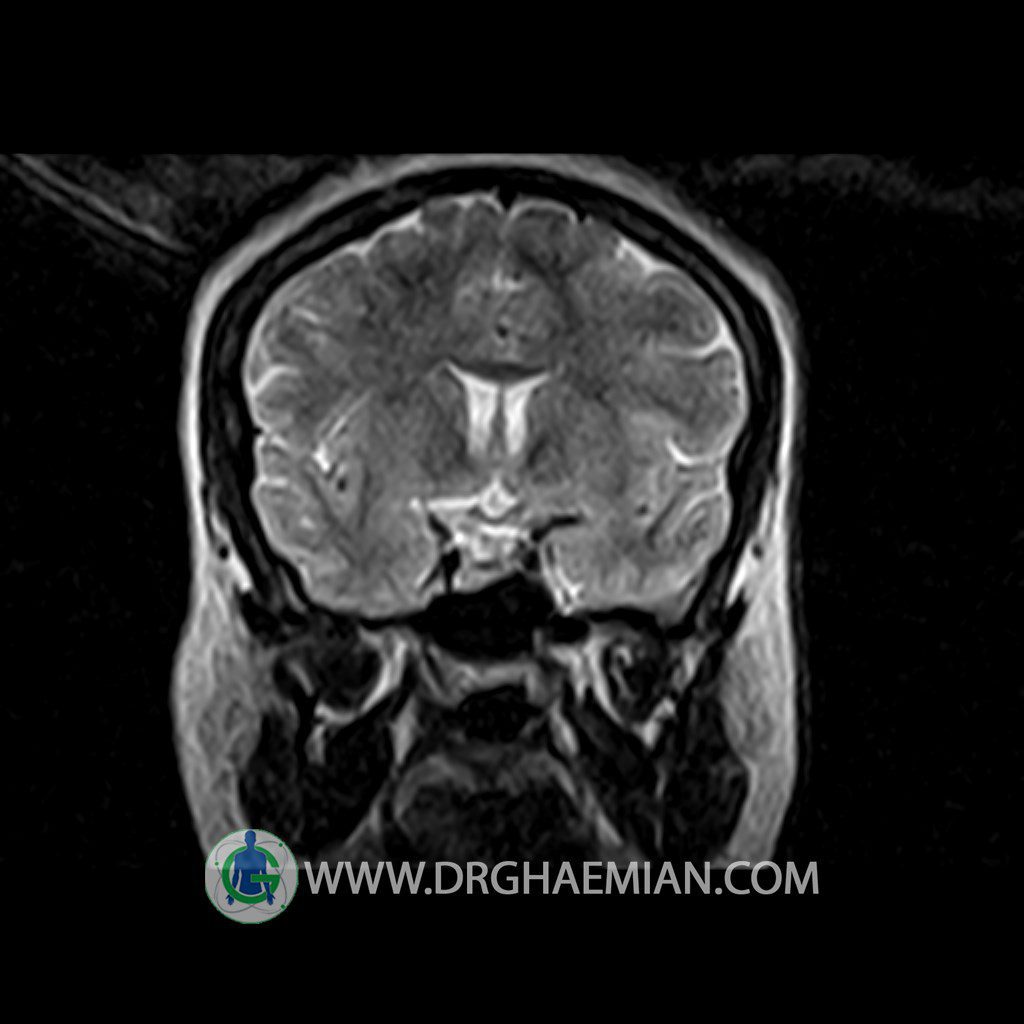

ام آر آی هیپوفیز یک روش تصویر برداری است که از غده هیپوفیز (غده ایی کوچک در مغز که هرومون ها و دیگر غدد بدن را کنترل می کند) و ناحیه های پیرامونش در مغز تصاویری ایجاد می کند. در این کیس سلای نسبتا خالی در ناحیه هیپوفیز بیمار مشاهده می شود.

Technique: Axial , coronal T1 , Axial , coronal , sagittal T2 , Axial, coronal T1 post Gd & 64 dynamic thin coronal slices.

The cavernous sinus and imaged portions of the internal carotid artery and carotid siphon are unremarkable .

Evaluable portions of the neurocranium show no abnormalities .

– Extension of suprasella cistern to sella with thin pituitary gland in floor of sella ( partial empty sella )

is seen